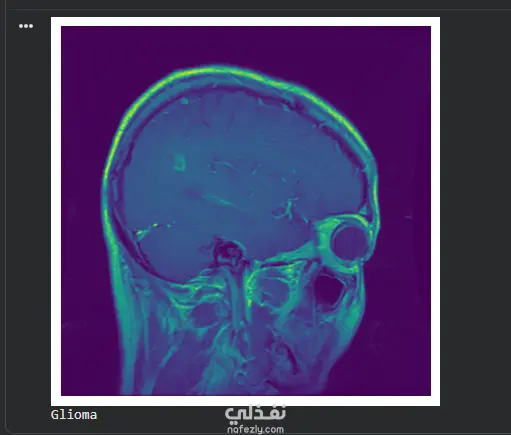

مشروع متكامل في مجال الذكاء الاصطناعي (Machine Learning) يهدف إلى دعم التشخيص الطبي من خلال تحليل صور الرنين المغناطيسي (MRI) لاكتشاف وتصنيف أورام الدماغ بدقة عالية. أبرز ما تم تنفيذه في المشروع: معالجة البيانات (Data Preprocessing): تنظيف وتحسين الصور الطبية لزيادة الوضوح وتقليل الضوضاء لضمان دقة النتائج. بناء النموذج (Modeling): استخدام تقنيات التعلم العميق (Deep Learning) وخوارزميات الـ CNN لبناء نموذج قادر على التمييز بين أنواع الأورام المختلفة. التقييم (Evaluation): اختبار النموذج والتأكد من تحقيقه لمعدلات دقة (Accuracy) و Precision عالية لتجنب الأخطاء في التشخيص. Optimization: تحسين أداء الموديل ليكون خفيفاً وسريعاً في استخراج النتائج.